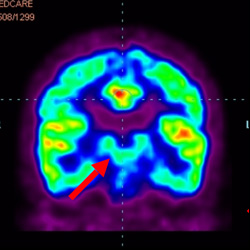

細胞治療前PET CT掃描顯示神經(jīng)組織中的藍/黑色區(qū)域,表明腦癱引起的大腦損傷。

腦癱細胞療法, 腦癱治療

細胞治療后,藍色和黑色區(qū)域減少,并且看到更活躍的區(qū)域。這表明損傷減少并改善了大腦功能。